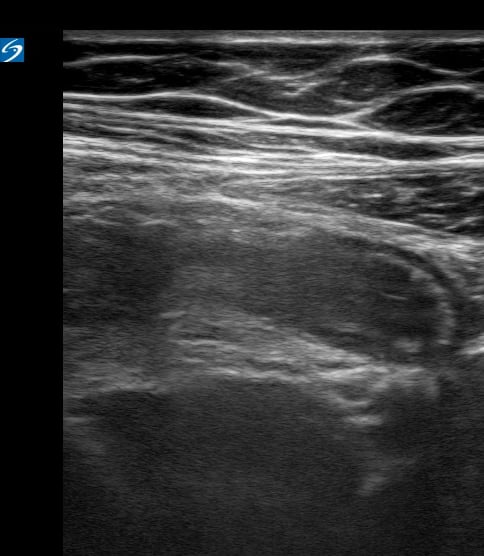

In pediatric ultrasound, appendicitis refers to the acute inflammation of the appendix, a common cause of abdominal pain in children. Ultrasound is a crucial diagnostic tool for appendicitis in pediatrics, offering a non-invasive way to visualize the inflamed appendix, which often appears as a non-compressible, blind-ending, tubular structure with a thickened wall and increased vascularity on color Doppler.

Early and accurate diagnosis of pediatric appendicitis via medical ultrasound helps avoid complications and guides timely surgical intervention, improving patient outcomes. Key ultrasound findings include target sign, pericecal fluid, and appendicolith. Understanding these sonographic signs is vital for effective pediatric emergency and surgical care.